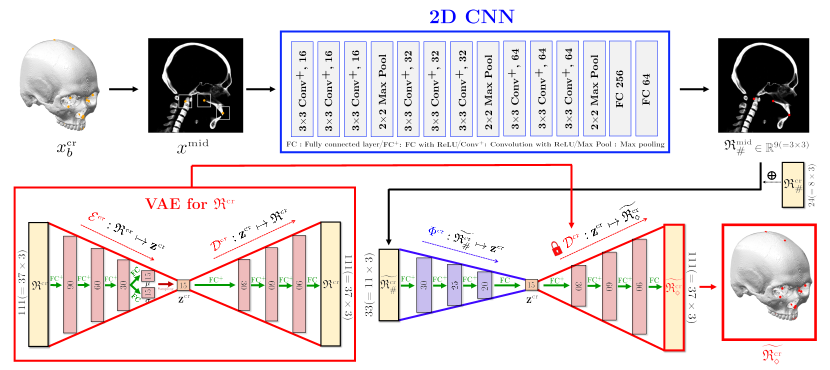

The proposed method attempts to address this problem by taking advantage of a semi-supervised learning framework that permits the utilization of the number of anonymized landmark data whose corresponding CT data are not provided. As shown in Figure 1, the proposed method comprises the following three main steps: (i) To obtain easy-to-find reference landmarks , we apply CNN with 2D illuminated images generated from a binarized CT image and normalize the output with respect to the cranial volume. (ii) A rough estimation of entire landmarks is obtained using the partial knowledge and a VAE-based low dimensional representation of . (iii) Using this estimation, coarse-to-fine detection for is conducted, wherein separate strategies are utilized for the mandibular and cranial landmarks. For the mandibular landmarks, the landmarks are accurately identified by applying 3D patch-based CNNs to capture the morphological features on a 3D surface geometry associated with the landmarks, wherein an input patch is extracted based on the coarse estimation. For cranial landmarks, we first detect three landmarks lying on the midsagittal plane by applying a 2D CNN whose input is an extracted 2D patch from a partially integrated image in basis of the coarse estimation. By utilizing the three finely-detected landmarks and cranial reference landmarks as the partial information of , the remaining cranial landmarks are finely annotated via a VAE-based local-to-global estimation utilizing the same method in the previous step .

2.2 Rough estimation of all landmarks from reference landmarks using VAE-based low dimensional representation

This section provides a method for roughly estimating all landmarks from the reference landmarks that are accurately annotated in the previous step. Based on the method in [Yun2020], we build a bridge that connects and by taking advantage of a low dimensional representation of learned by a variational autoencoder (VAE) [Kingma2013].

where is a local-to-global landmark estimation map as described in Figure 3. The map is constructed via the following process.

where the matrices represent fully-connected layers. The detailed network architecture is described in Figure 3.

where can be obtained by the trained encoder and is a set of all functions that can be learned via the fully-connected network structure. The detailed architecture of the map is described in Figure 3.

The training of uses only the landmark dataset . Based on patterns learned from the landmark dataset, we are able to estimate all landmarks from the partial knowledge . By utilizing the given CT image data, therefore, we put a final touch on the rough estimation to achieve more accurate landmark placement.

2.3.2 Detection of cranial landmarks

Let be a concatenated positional vector with cranial reference landmarks and three finely detected landmarks obtained by . Using this partial knowledge , we find accurate cranial landmark positions via

where is a nonlinear map and is a decoder of VAE. Here, is a -dimensional latent variable given by and is an encoder of VAE. The maps and are trained in the same method presented in (5) and (10) using cranial landmarks . The detailed architectures of and are illustrated in Figure 5.